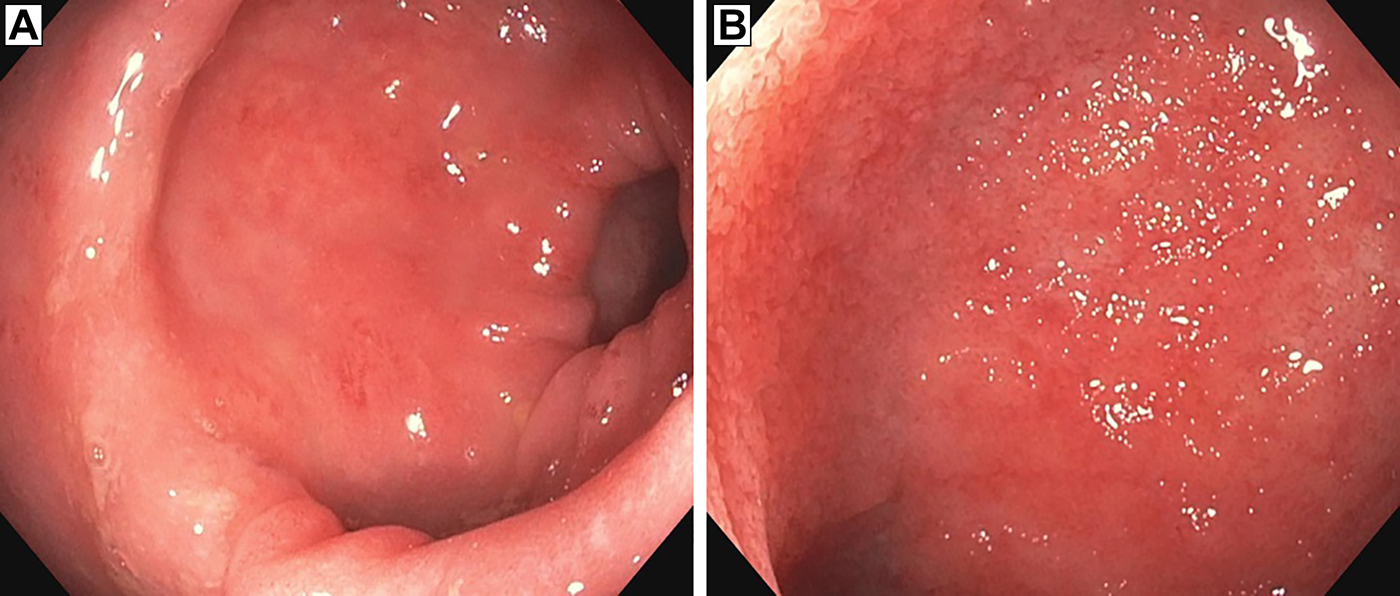

The patient underwent GI tract esophagogastroduodenoscopy 24 hours after admission. Results revealed severely inflamed, diffusely erythematous mucosa in the stomach (Figure 1A) and diffusely erythematous, congested mucosa with overlying exudate in the duodenum (Figure 1B). Gastric biopsy specimens demonstrated focally active gastritis without granuloma formation (Figure 2). Giemsa stain results were negative for Helicobacter pylori. Duodenal biopsy specimens showed active duodenitis with acute cryptitis, crypt abscess formation, and mild villous blunting without granulomas or viral inclusions (Figure 3). Results of colonoscopy with examination of the terminal ileum revealed mild colonic inflammation, extending from the rectum to the mid-ascending colon (Figure 4A). The most severe condition appeared to be in a rectosigmoid distribution. The proximal ascending colon and cecum appeared to be spared. The ileal mucosa appeared erythematous and edematous, with overlying exudate (Figure 4B). Biopsy specimens of the rectum, the sigmoid, and descending, transverse, and proximal ascending colon demonstrated mild active colitis with acute cryptitis, crypt abscesses, and neutrophils within the lamina propria (Figure 5). Biopsy specimens of the distal ileum showed moderate active ileitis with acute cryptitis, crypt abscesses, and focal architectural distortion (Figure 6).

Colonoscopy with examination of the terminal ileum taken 2 weeks after ipilimumab administration showed (A) mild colonic inflammation, extending from the rectum to the mid-ascending colon and (B) erythematous and edematous ileal mucosa.